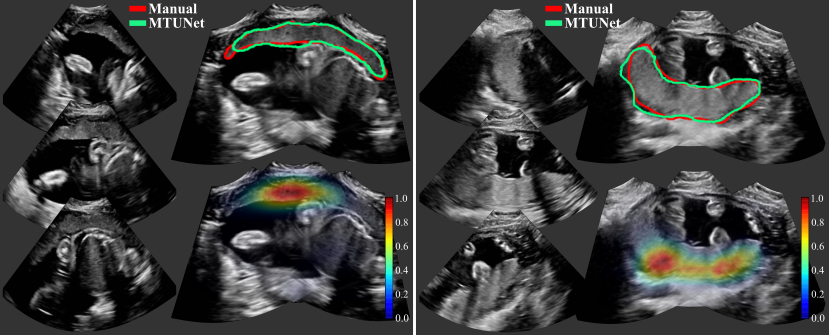

Examplary multi-view images are shown in Fig. 5 with corresponding placenta segmentations with MTUNet and combined attention maps. The placenta is better visualized in the multi-view images with reduced image artifacts and an extended FoV. The multi-task model MTUNet provides an accurate segmentation and the combined attention maps localize well the placenta. Further examples of multi-view images with corresponding segmentations can be found in Fig. 12 in the appendix.

We show attention maps obtained by models EncNet and MTUNet in Fig. 3. In EncNet, the model’s attention lies rather at the boundary of the placenta and surrounding tissue/space than on the placenta itself. The additional training on segmentation in model MTUNet, yields attention maps with good placenta localization.